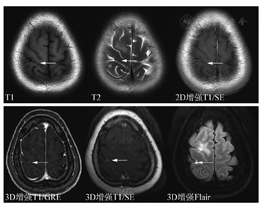

最低标准中,核心是强调了薄层扫描。3D是各向同性块扫描,重建后的单层图像可达到1mm或者0.6mm薄层厚度。共识建议3D扫描,如果不能进行3D扫描,2D扫描层厚要求是3mm;在序列选择方面,首选SE序列。SE是经典MRI序列,病灶显示度高,但扫描时间略长。如果不能进行增强后3DSE序列扫描而使用了3DGRE序列扫描(优点是快,缺点是由于白质信号增高而导致病灶对比度不够,皮质浅表病灶显示差,由于不能附加压脂导致颅骨转移瘤显示差,以及亮血效应带来的脑沟内血管过度显示),建议增加一个增强后2DSE序列。各序列实例比较见图2。

另外,DWI由于非常有诊断价值和扫描时间短,建议始终放在平扫序列里。而注射造影剂前的平扫中,只扫Flair序列,T2放在增强后扫描。优化标准中,主要增加了DSC灌注扫描(可能对鉴别肿瘤复发和放射性坏死有用)、增强后Flair(显示软脑膜转移病变较常规增强T1MRI效果好)以及增强后长时间延迟扫描(60~105 min,以期显示小病灶)。关于增强后Flair序列,对于脑膜转移的增强显示能力已被认可。对于脑实质内的转移瘤病灶,并不能增加诊断信息,但是对于靠近皮质的表浅病灶,显示能力超过常规增强T1,详见图3、图4。不同MR扫描机的序列名称不同,但序列的本质一致。

GRE序列增强,由于不能附加压脂,会导致遗漏颅骨转移病灶,因此也是共识建议增强后增加一个2DSE序列的理由。但平扫DWI序列中附加了压脂,颅骨转移瘤一般平扫中会引起怀疑。

关于软脑膜转移,常规增强T1SE序列常难以发现,GRE序列由于血管增强效应,会导致脑沟内多发的条状或者点状高信号,即高估效应,带来假脑膜转移瘤征象。近年来,增强后Flair序列在显示脑膜转移瘤方面显示出一定优势,尤其在一定时间的延迟后,更可以确认脑膜转移的有无,从而准确评估预后和制定治疗决策。